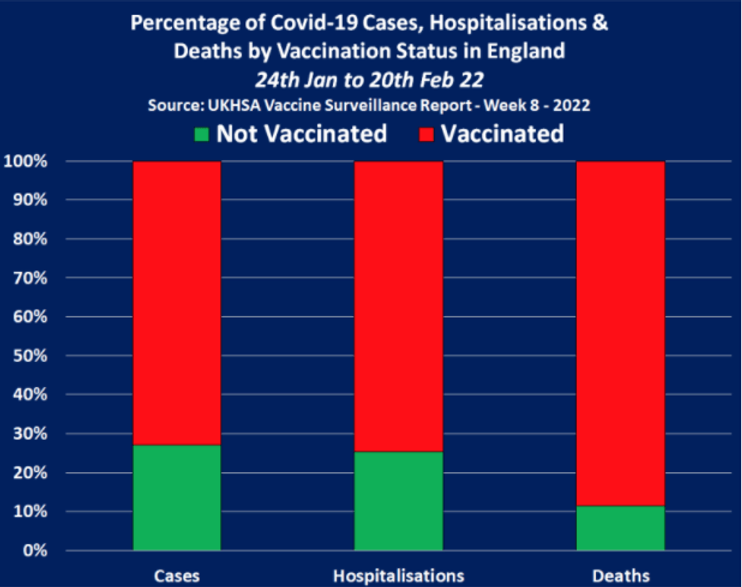

Table 10, found on page 41 of the latest report shows the number of Covid-19 cases by vaccination status in England between 24th of January and the 20th of February, 2022, and it confirms the vast majority were recorded among the triple vaccinated population.

In all, between the 24th of January and the 20th of February, there were a total of 1,490,464 Covid-19 cases recorded across England, and the triple vaccinated population accounted for 752,126 of them, whilst the not-vaccinated population accounted for 404,030 of them but 303,107 of those cases were among children.

Overall the vaccinated population accounted for 1,086,434 cases, meaning they accounted for 73% of all Covid-19 cases between the 24th of January and the 20th of February 2022. But, if we remove children from the equation we find that the vaccinated population accounted for 91% of all Covid-19 cases among over 18 year old’s in England.

Table 11, found on page 42 of the latest report shows the number of Covid-19 hospitalizations by vaccination status in England between the 24th of January and the 20th of February, 2022, confirms the vast majority were again recorded among the triple vaccinated population.

In all, there were 9,230 Covid-19 hospitalizations in England between the 24th of January and the 20th of February, 2022, and the triple vaccinated population accounted for 4,936 of them, whilst the nonvaccinated population accounted for 2,341 of them, 1,132 of which were allegedly children.

When we include children in the hospitalization figures we find that the vaccinated population accounted for 75% of all Covid-19 hospitalizations between the 24th of January and the 20th of February, 2022. But when we remove children, we find that the vaccinated population accounted for 85% of all Covid-19 hospitalizations among over 18’s in England.

Table 12, found on page 43 of the latest report shows the number of Covid-19 deaths by vaccination status in England between the 24th of January and the 20th of February, 2022, and it confirms yet again that the vast majority were recorded among the triple vaccinated population.

In all, there were 4,861 Covid-19 deaths between 24th of January and the 20th of February, 2022, and the triple vaccinated population accounted for 3,120 deaths. Whilst the nonvaccinated population accounted for just 559 deaths.

Overall, the vaccinated population accounted for 89% of all Covid-19 deaths during these four weeks, with 4,302 recorded deaths. This means the vaccinated population now account for 9 in every 10 deaths, and the triple vaccinated population account for 4 in every 5 deaths.